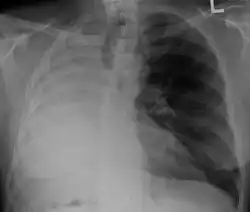

Left tension pneumothorax with a large, well-demarcated area devoid of lung markings with tracheal deviation and movement of the heart away from the affected side. |

Tension pneumothorax

Tension pneumothorax is an emergent condition in which air gets trapped in the space between the chest wall and the lung. This space is referred to as the pleural space. Because air can't escape from this space, the air pocket grows larger and larger, resulting in the lung collapse closest to the pneumothorax. Forces are transmitted to the mediastinum and effectively "push" the mediastinal structures to the opposite side of the chest.[5]